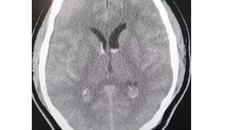

Hình ảnh phim chụp xuất huyết dưới nhện lan tỏa - tụ máu não thất. (Ảnh: Nhân Dân)

(Ngày Nay) -  Nhờ phối hợp nhịp nhàng, hiệu quả nhiều chuyên khoa, các bác sĩ Bệnh viện Bạch Mai đã cứu sống bệnh nhân Bae Hyo Nam bị chảy máu dưới nhện thể nặng.